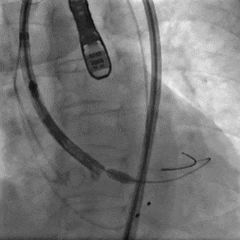

术中影像

左冠造影

左冠狭窄处行PCI处理

PCI后左冠造影,血流通畅

右冠造影

右冠狭窄处行PCI处理

PCI后右冠造影,血流通畅